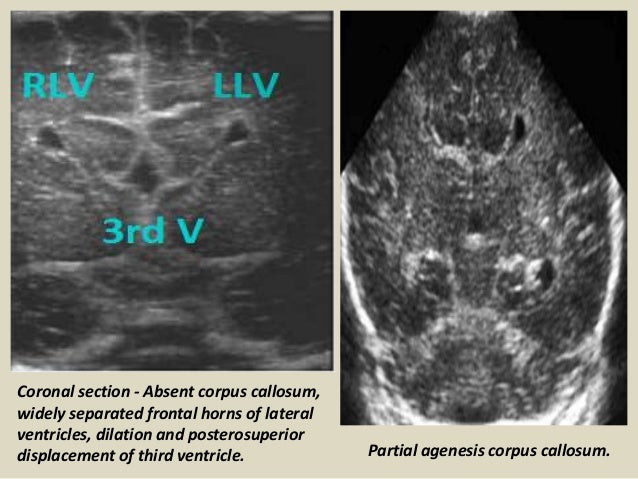

29. 29. Coronal section - Absent corpus callosum, widely separated frontal horns of lateral ventricles, dilation and posterosuperior displacement of third ventricle. Partial agenesis corpus callosum.